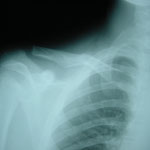

●右鎖骨骨折

当患者さんは手術療法に強く抵抗があり当院での保存療法を選択されました。

骨折部位の短縮転移があたので整復操作が必須になります。運よく短縮転移が矯正されたので保存療法で経過をみました。暑い時期だったので来院の度に固定を外し体を清拭して施術後、新しい下着の上から再度固定をする運びになりました。

骨折部位には超音波、患部以外の所は関節運動、経過を見て軽いマッサージを開始。固定も少しずつ簡易な物へ変更し二カ月後には三角巾のみ、三ヵ月経過すると肩関節の挙上もできるようになりました。

経過良好で完治しました。

左のレントゲンは短縮転位 (受傷時) 右は整復操作をして骨片が重なり合っている状態